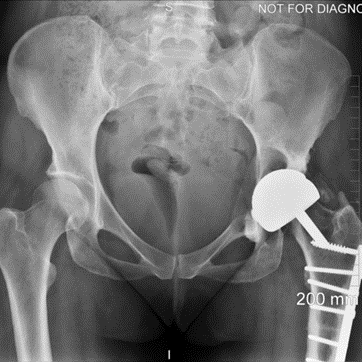

The patient, a 49-year-old woman, underwent metal-on-metal (MoM) hip resurfacing procedure in 2001 due to a unilateral hip dysplasia (DDH). 17 years later, she presented with mild hip pain but extensive loss of bone in the pelvis which was presumably caused by an inflammatory reaction to metal wear debris. Her blood metal ion levels were 100 times higher (cobalt 188 bbp and chromium 126 bbp) than from patients with well-functioning MoM hips.

The case posed multiple challenges. The patient was at imminent risk of pelvic fracture without surgery. However, surgery itself also risked fracture of the pelvis during implant removal. Furthermore, the remaining pelvic bone was poisoned by metal debris and thus the patient’s bone integrity was compromised, which could affect the stability of a new implant.

A multidisciplinary team decided that revision surgery was necessary due to the risk of fracture and very high metal ion levels. The plan involved removing the existing MoM implant and fitting a custom 3D-printed acetabular cup. The procedure required meticulous care to avoid causing fractures during implant removal. The new cup would only be effective if the pelvis remained intact.

The operation was successful, with minimal bone loss during implant removal. A custom-made titanium acetabular cup was fitted and stabilized with screws. Postoperative imaging confirmed correct implant positioning and satisfactory fixation. The patient’s recovery was positive, with significant reductions in metal ion levels and the restoration of pain-free hip function.

This case represents ALTR with MoM, which was characterized by extensive osteolysis of pelvic bone, which was presumably caused by metal wear debris. Elevated blood levels of chromium and cobalt further supported this hypothesis.

This case demonstrates the importance of precise surgical planning and execution in complex hip revision surgeries. The use of 3D-printed implants tailored to the patient's anatomy greatly improved the chances of successful fixation despite significant bone loss. Update at 6 years post operative is that the patient living a full and active life with excellent hip function. More details about this type of surgery has been published by Professor Hart: